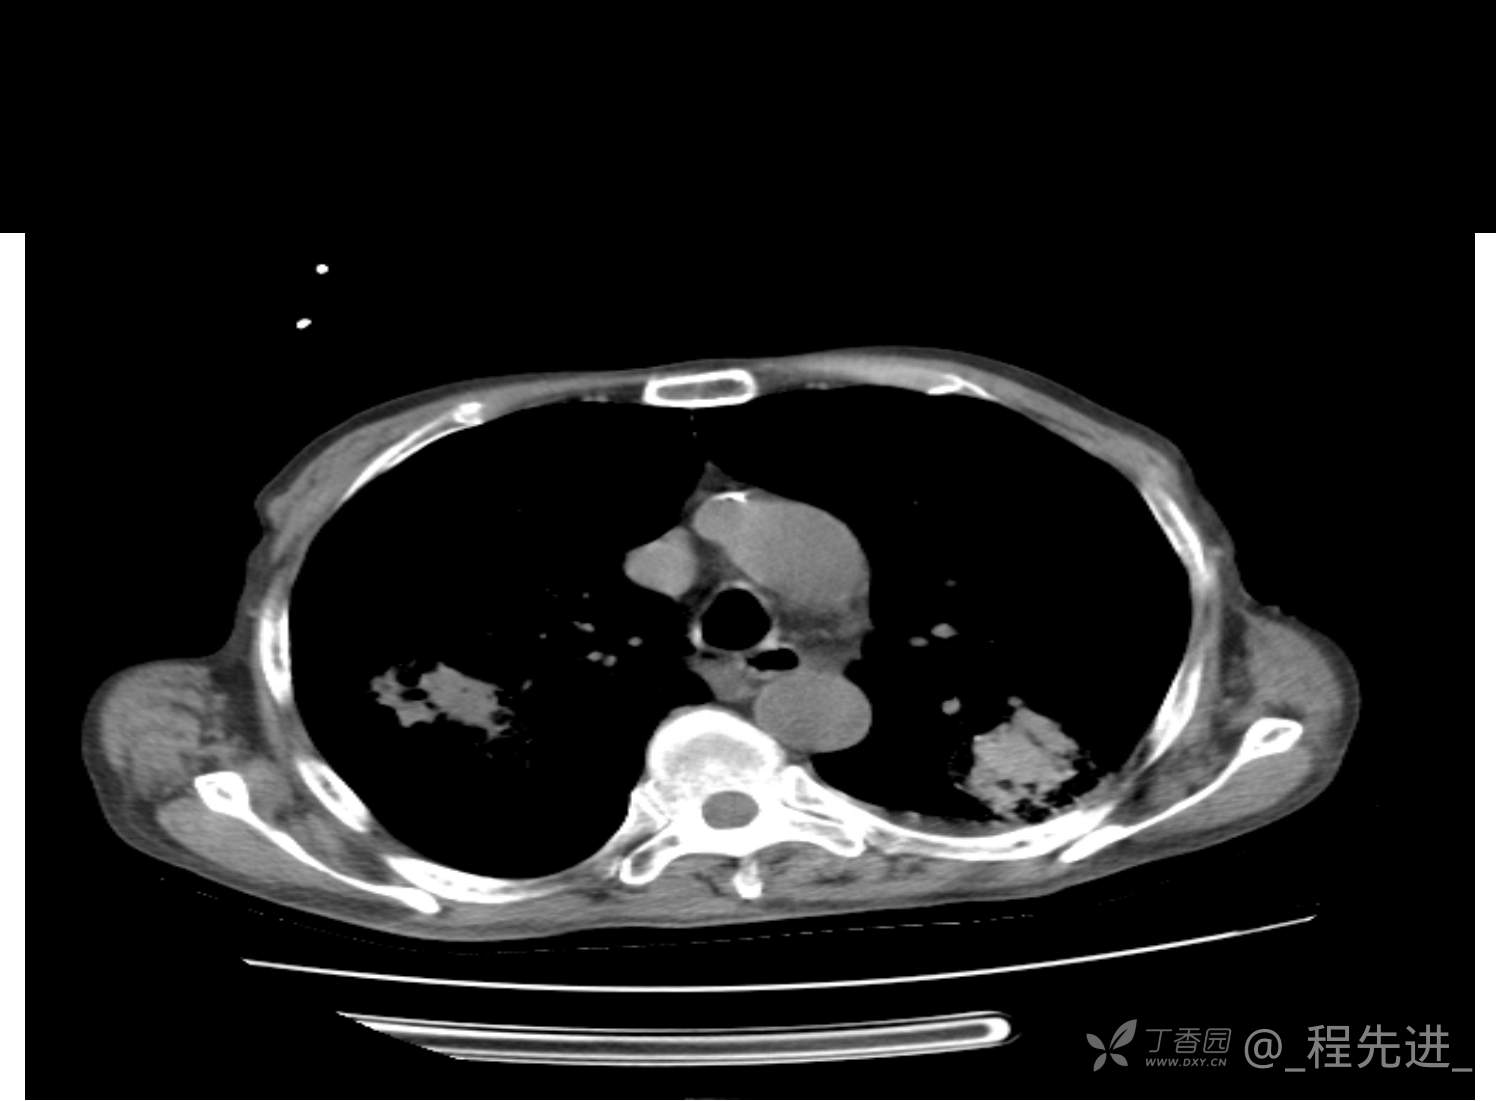

患者性别:男

患者年龄:81岁

简要病史:反复咳嗽、咳痰20余年,加重1周。两肺呼吸音低,可闻及散在干湿啰音。